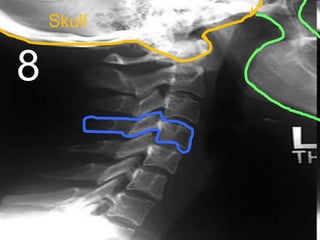

• Your brain is protected by the skull case

Copyright © 2010 Ryan P. Murphy

• Traumatic brain injury (TBI)

– A blow to the head that disrupts normal brain

function.

– A mild blow to the head can result in being

knocked unconscious.

• Repetitive collisions / concussions can

cause a number of serious brain

functioning problems later on in life.

– 50,000 people in the U.S. die each year

– Most occur from falls and motor vehicle

accidents.

– In severe cases your brain doesn’t function

well anymore.